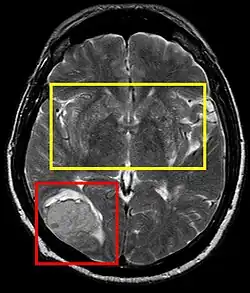

| Stroke brain (similar to cerebral softening) | |